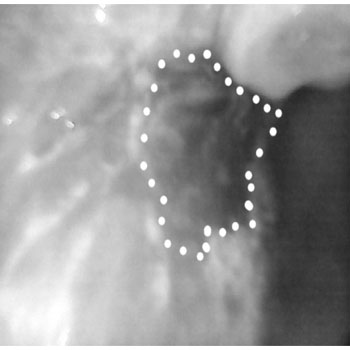

clinical Image and Image of the lesion Under the influence of Blue light, we can appreciate the difference in the extent of the lesion under white light and blue light. The blue light used with low intensity.

With Low intensity of light, with high intensity of light , we can appreciate the reflection with enamel which is adjacent to the lesion, thus masking some part of the lesion

same lesion with the camera in the device with low intensity of light